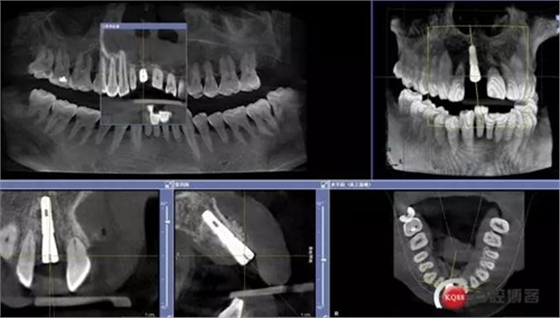

術(shù)前CBCT

術(shù)后CBCT